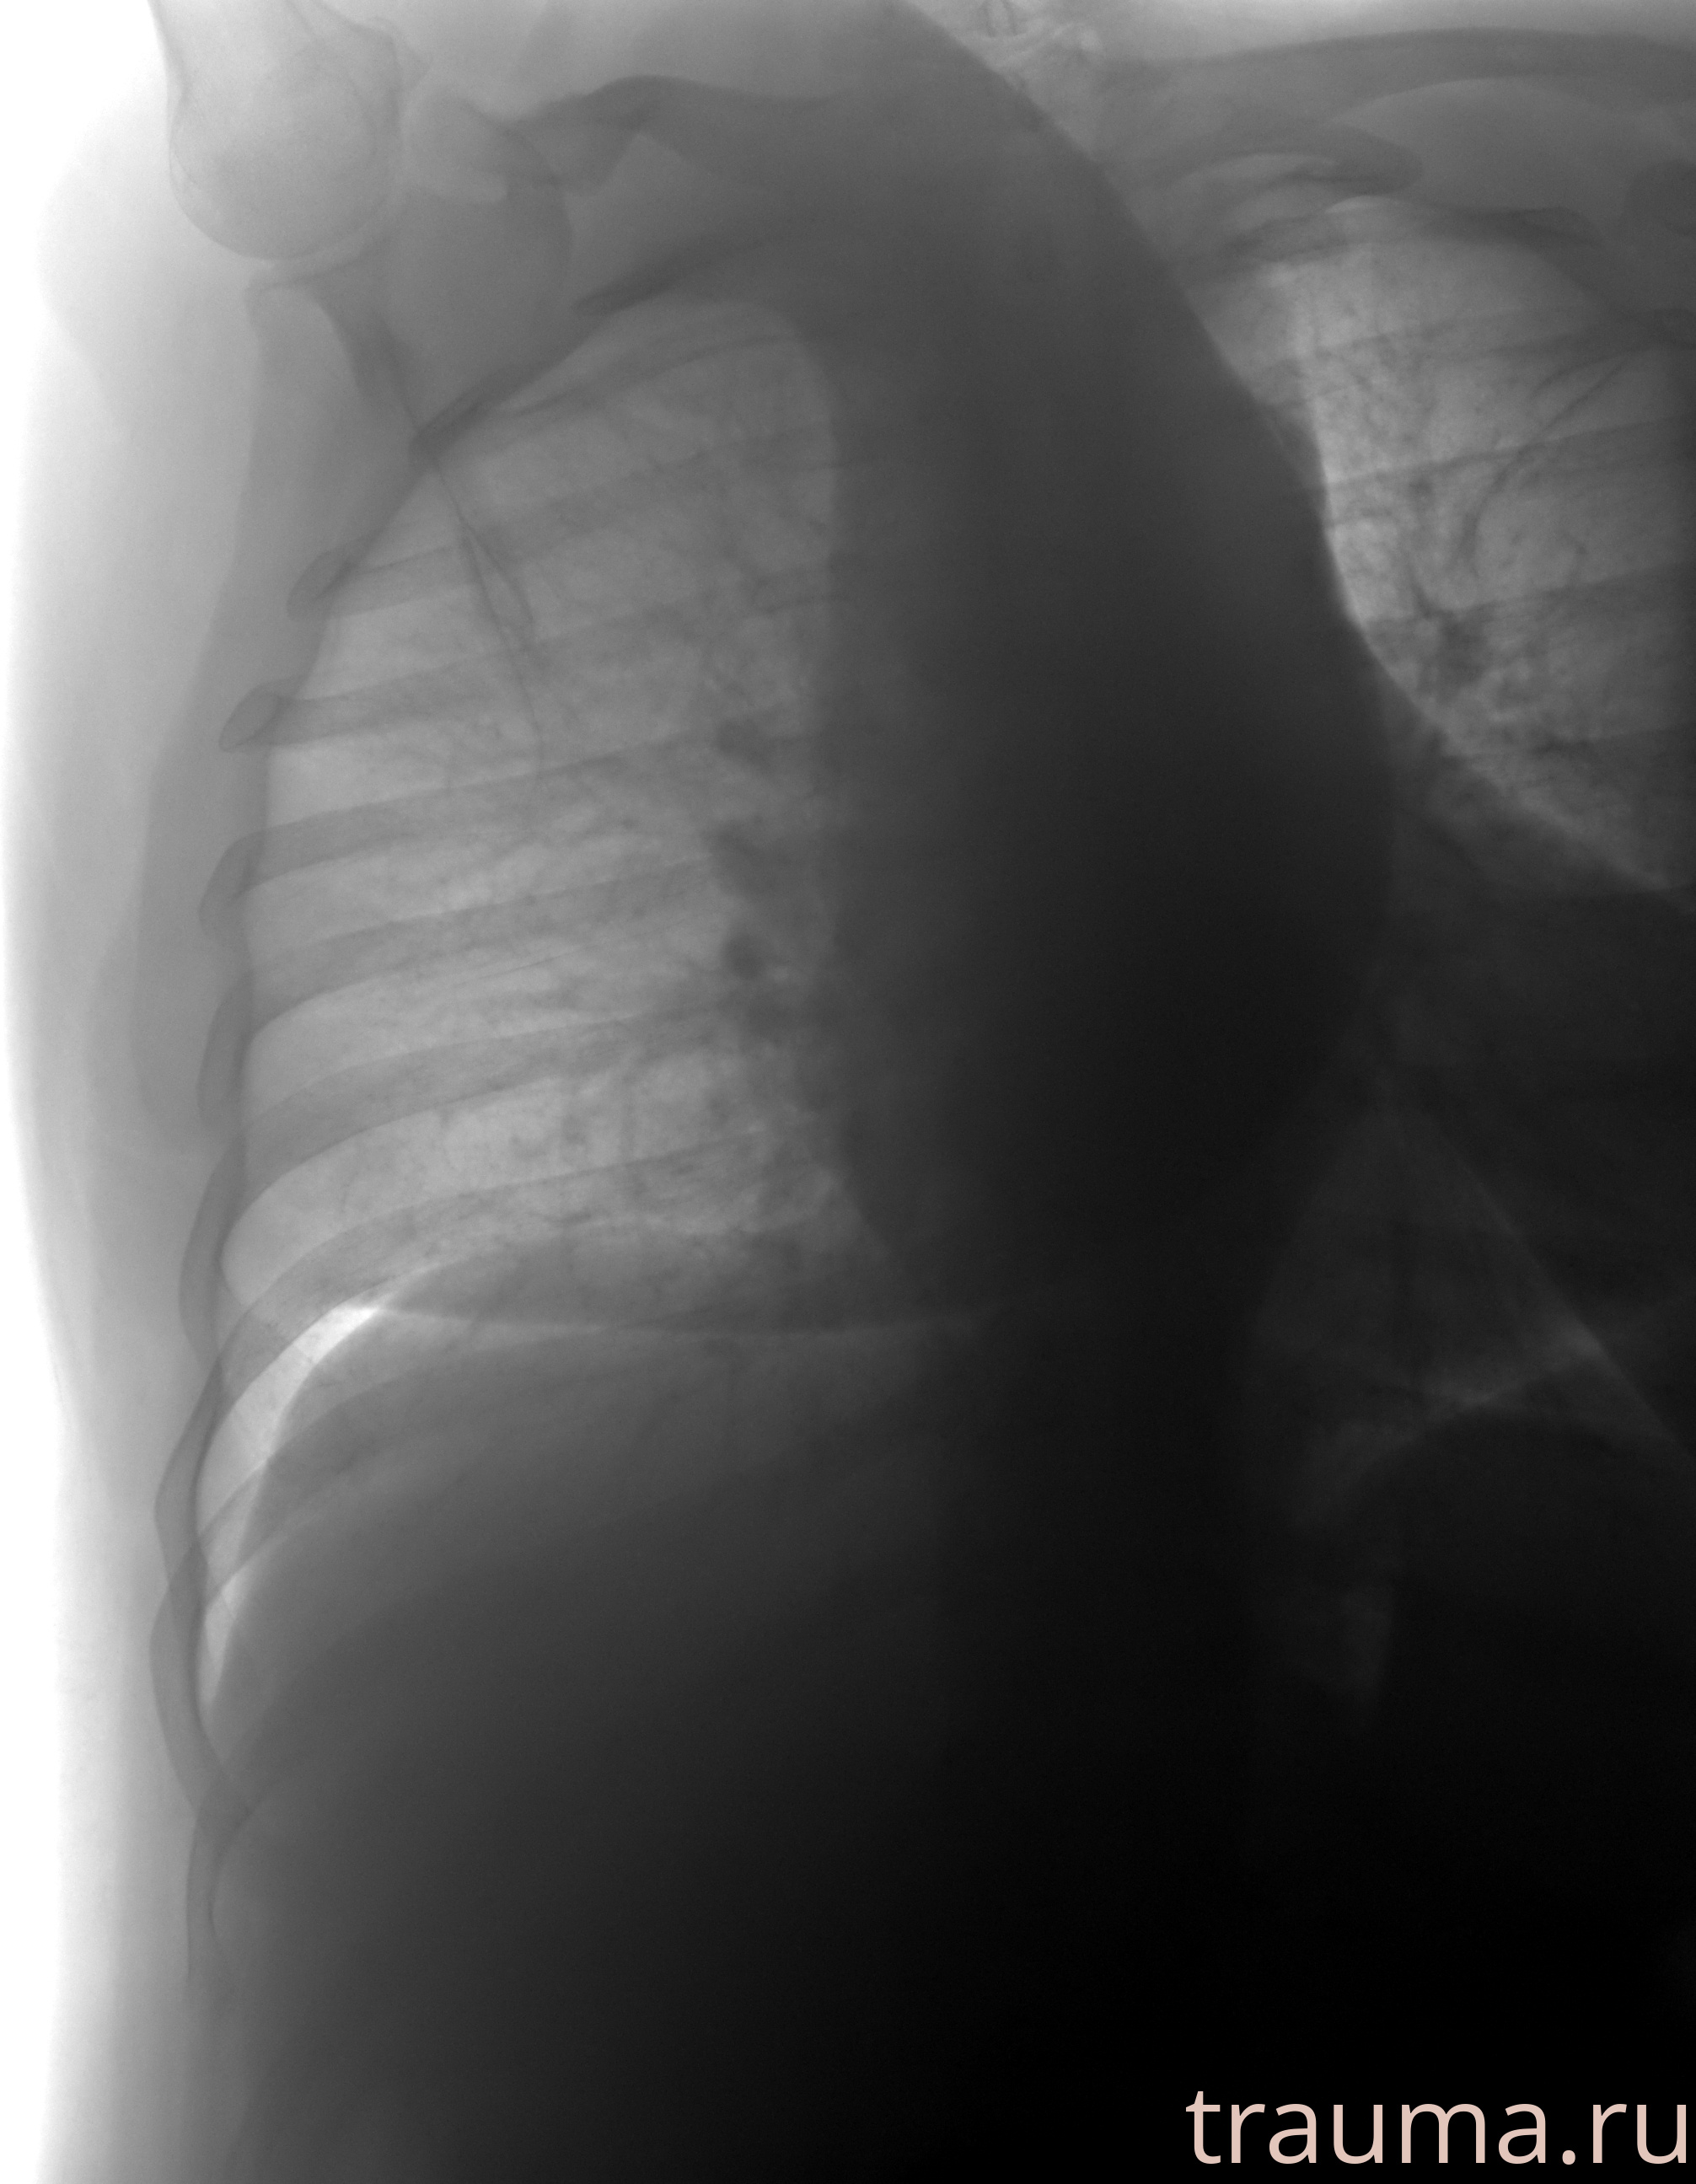

Рентгенограммы

Рентген на дому: по вашему адресу приезжает врач-рентгенолог, травматолог-ортопед с мобильным рентгеновским аппаратом, проводит диагностику травмы или заболевания, делает необходимые рентгенограммы, дает рекомендации по дальнейшему лечению. Получить качественные снимки в домашних условиях возможно благодаря уникальной методике, разработанной МосРентген Центром для института  Склифосовского